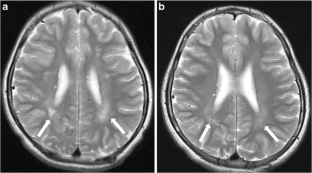

Fig. 1